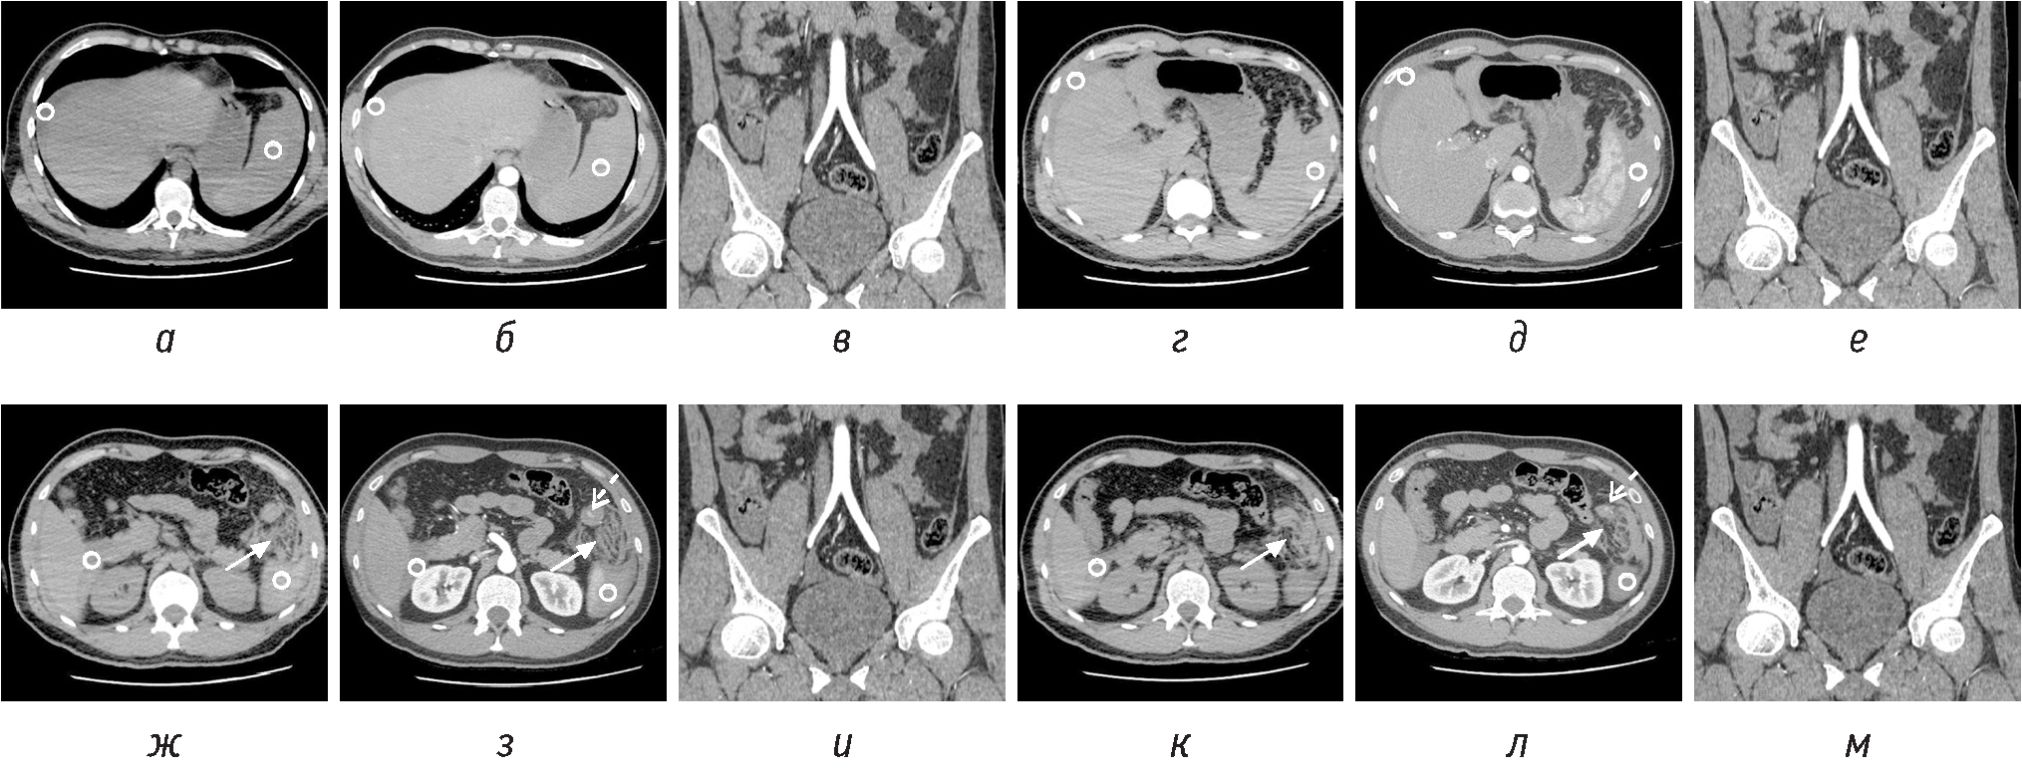

Пациенту провели УЗИ, КТ с внутривенным введением контрастного вещества. По данным УЗИ (снимки не предоставлены) по внешнему контуру селезенки аваскулярное неоднородное содержимое повышенной эхогенности (вероятно, подкапсульно) толщиной 22 мм (подкапсульная гематома?). Свободная жидкость в брюшной полости визуализируется кпереди от печени толщиной до 9 мм, под печенью — до 20 мм, по правому фланку толщиной до 20 мм, под селезенкой — 5 мм, со сгустками (вероятно, кровь). Сразу после УЗИ провели контрастусиленную КТ груди, живота, таза. По данным КТ признаки разрыва селезенки с подкапсульной гематомой и распространением геморрагического содержимого, скоплением его в малом тазу, вокруг печени, по боковым фланкам: селезенка 105 × 35 × 91 мм, с ровными четкими и нечеткими контурами, ее плотность в центральных отделах +62 HU, вдоль латеральной поверхности и нижнего контура отмечается скопление содержимого (+49…60 HU) толщиной 28…30…38 мм, паралиенальная клетчатка неравномерно уплотнена, тяжиста; гиперденсное содержимое протяженно распространяется по левому латеральному карману до крыла левой подвздошной кости. Также жидкость визуализируется по большой кривизне желудка, диафрагмальной поверхности печени, спускаясь по правому боковому карману до малого таза (рис. 1, а–в). В малом тазу — скопление незначительного количества жидкостного содержимого толщиной 10 мм и плотностью +32…38 HU.

Рис. 1. КТ-изображения в аксиальной плоскости в нативную (а, г, ж, к) и артериальную фазу (б, д, з, л), соответствующие секущей линии на изображении в артериальную фазу во фронтальной плоскости (в, е, и, м) на разных уровнях. Гематома в левом верхнем квадранте большого сальника в виде имбибиции жировой клетчатки и жидкостного скопления (белая стрелка). Экстравазация из сальниковой артерии (белая пунктирная стрелка). Гемоперитонеум (круг)